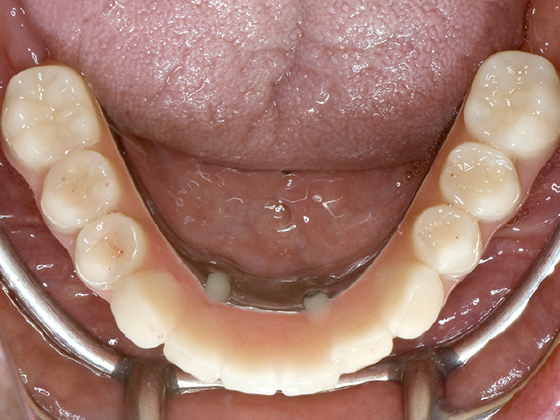

最終補綴物装着

下顎の歯がしっかりと固定され、きちんと噛めるようになりました。

仮歯装着